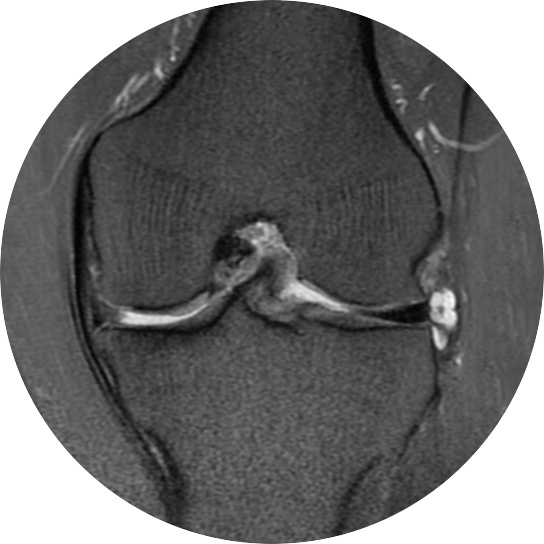

연골손상의 단계를 결정할 때 사용하는 ICRS 단계에서 3단계 미만의 연골손상에 사용하는 방법으로 울퉁불퉁한 표면을 다듬어 주는 정도의 수술법입니다.

4단계 이상일 경우 미세천공술을 기본으로 시행하며, 미세천공술로 나온 본인의 골수줄기세포와 함께

연골 생성을 촉진할 수 있는 “재료”를 같이 주입하는 치료를 시행합니다.

손상된 연골 부위에 작은 구멍을 뚫어 골수에서 나오는 줄기세포를 이용하여 연골 재생을 유도하는 방법으로 근본적으로 섬유연골(정상연골보다는 약한 연골)로 재생된다고 알려져 있습니다.

특수하게 농축하여 제작된 6% 콜라겐(리젠실603) 또는 9% 콜라겐(이엔카티)을 천공술을 시행한 부위에 덮어 주어 미세천공술 단독보다 좋은 치료 결과를 기대할 수 있습니다.